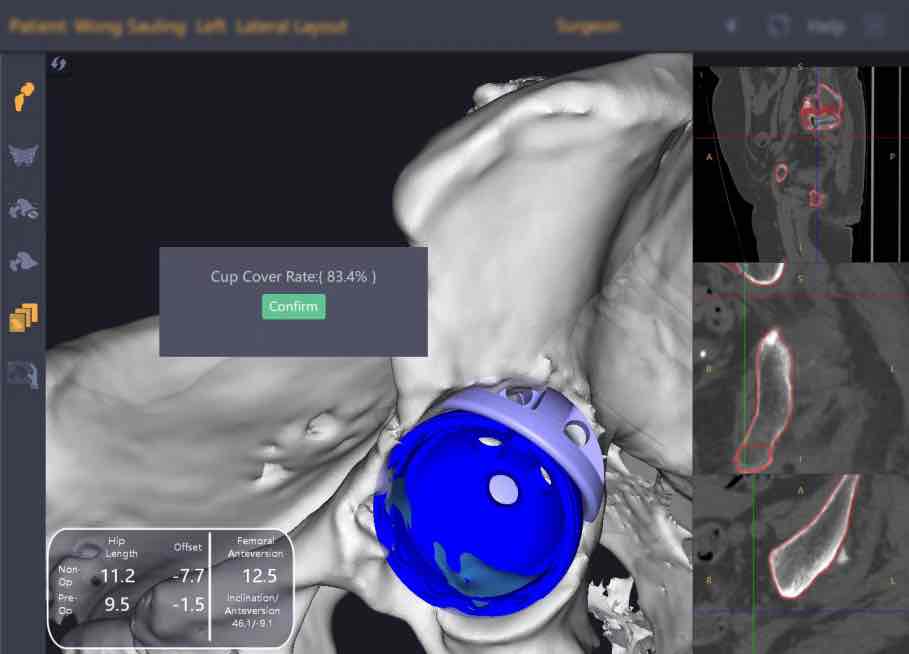

患者为一名长期受重度髋关节疼痛及功能障碍困扰的老年人,影像学显示其髋臼存在罕见的双区域骨缺损,传统术式如高位髋中心、Jumbo杯或单一Augment等均难以兼顾假体稳定性与解剖复位需求。面对这一临床难题,蔡子龙医生团队借助锟铻®机器人强大的亚毫米级三维重建、智能规划与实时导航能力,首创将两个Augment模块拼合使用,构建出定制化的“Footing假体”——如同为髋臼假体打造一个精准贴合的“生物型基座”,不仅显著提升骨覆盖率,更将关节旋转中心恢复至生理位置,从根本上保障假体长期存活率。

在锟铻®机器人引导下,团队首先完成髋臼缺损区域的精准打磨,随后高效成型髋臼窝,并在导航探针实时指引下,将组合式“Footing假体”严丝合缝植入预定位置,最终稳妥置入髋臼杯。全程操作高度还原术前数字规划,真正实现“所见即所得、规划即手术”的精准医疗理念。